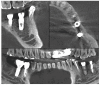

The purpose of this review is to examine various assessment methods in order to compare the accuracy between the virtually planned and clinically achieved implant positions. In this review, comparison methods using pre- and post-operative computed topography (CT) data and digital impressions for definitive prosthesis will be described. The method for the displacement and strain for quantification of the error will also be explored. The difference between the planned and the actual implant placement position in guided implant surgery is expressed as an error. Assessing the accuracy of implant-guided surgery can play an important role as positive feedback in order to reduce errors. All of the assessment methods have their own inevitable errors and require careful interpretation in evaluation.